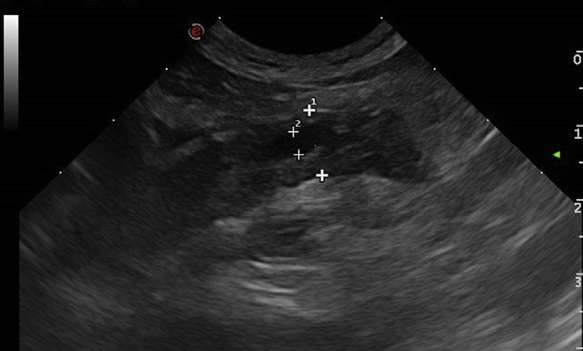

一般无法通过腹部X光片诊断,但可以发现腹膜炎的迹象或肿块效应。1,2,30超声检查是对猫 最有用的成像方式,可以发现胰腺肿大、回声变化、肿块效应、胰腺周围高回声和游离液体(图2)。2,5,31,32,42,43它还有助于发现其他重要的腹部疾病,如肿瘤,并识别胆管和肠道的并发变化。在一项对患有胆管炎的猫的研究中,有17只猫的肠壁出现了异常,7只猫的超声检查同时出现了胰腺异常。44一些变化,如胰腺管的直径增加,随着年龄的增长而正常发生,不应过度解释为反映胰腺炎。45,46在早期的研究中,与组织学相比,超声检查的敏感性是差到中等的(24%-56%)。3,30,42在这些研究之后的16年或更长时间里,技术的改进和临床医生的经验可能已经大大改善了敏感性。在最近的一篇文章中,43当Spec fPLI增加被认为是胰腺炎的诊断时,腹部超声检查的敏感性为84%,最敏感的单一超声检查发现是高回声的胰腺周围脂肪。同样,腹部超声检查和Spec fPLI对创伤性胰腺炎的诊断也有很好的相关性。47对猫的超声检查的特异性很少进行评估。Williams及其同事43,报告了75%的总体特异性,但是,当每个超声检查参数(胰腺厚度增加、胰腺 边缘异常、胰腺周围脂肪回声过高)被单独考虑时, 特异性增加到90%以上。如果这具有代表性,当超声检查是唯一的诊断检查时,诊断不足比诊断过度更有可能。

图2 急性胰腺炎猫的超声检查结果。注意胰腺低回声和增大,以及周围肠系膜高回声。胰管(由2个交叉点描绘)扩大,但这仍然是一个非特异性的发现。